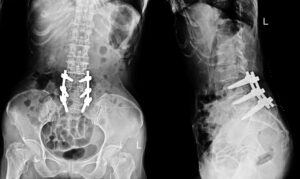

Patients diagnosed with lumbar spondylolysis and spondylolisthesis are sometimes referred to surgery. The main surgical procedures is spinal fusion, This surgery is designed to stabilize the spine and provide decompression to relieve pressure on the nerves. In spinal fusion, two vertebrae are joined together, frequently using instrumentation (rods and screws) and bone grafts; in decompression, … Continue reading Lumbar Spondylolysis And Spondylolisthesis Surgery Research